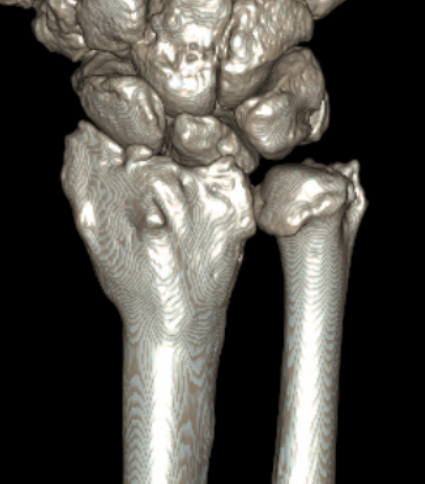

CT

CT guided 3D planning

- RCT of 40 patients with radial malunion

- 2D versus 3D planning and patient specific surgical guides

- 3 degree better correction in 3D group

- non significant trend towards better outcomes in 3D group

Intra-articular osteotomy

Indication

Step deformity

No radiocarpal osteoarthritis

Technique

Dorsal 3/4 approach and open radiocarpal joint